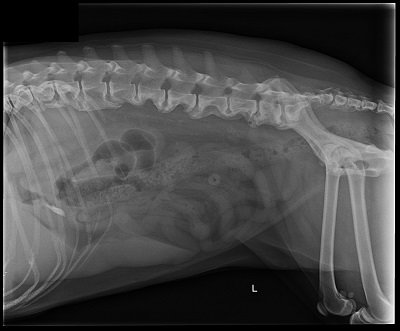

Question of the Day

Put your knowledge           to the test

Get a visual practice question delivered to your inbox daily.